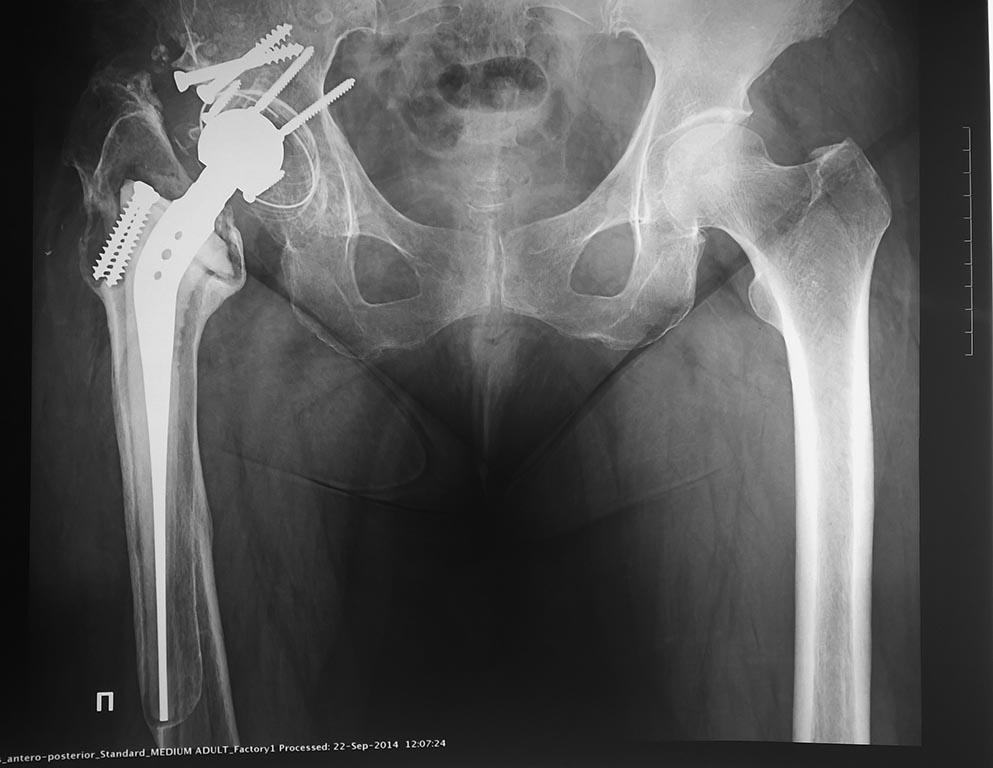

Итак, имеем такой вот рентген. Что за протез был установлен 17 лет

назад? Фото с ответом выложу

в понедельник. Лично я был мягко говоря весьма удивлен.